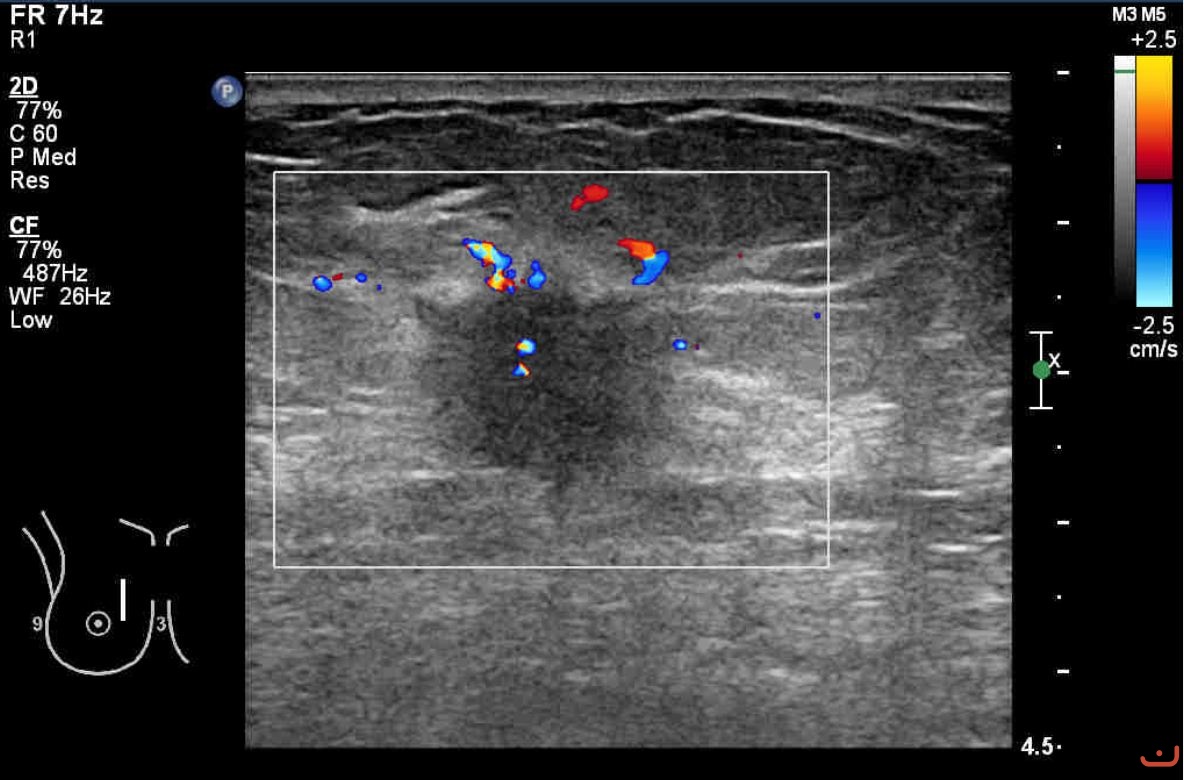

Benign solid mass

Date

Sunday, 16 August 2015

116.58 KB (1184 x 780 px)